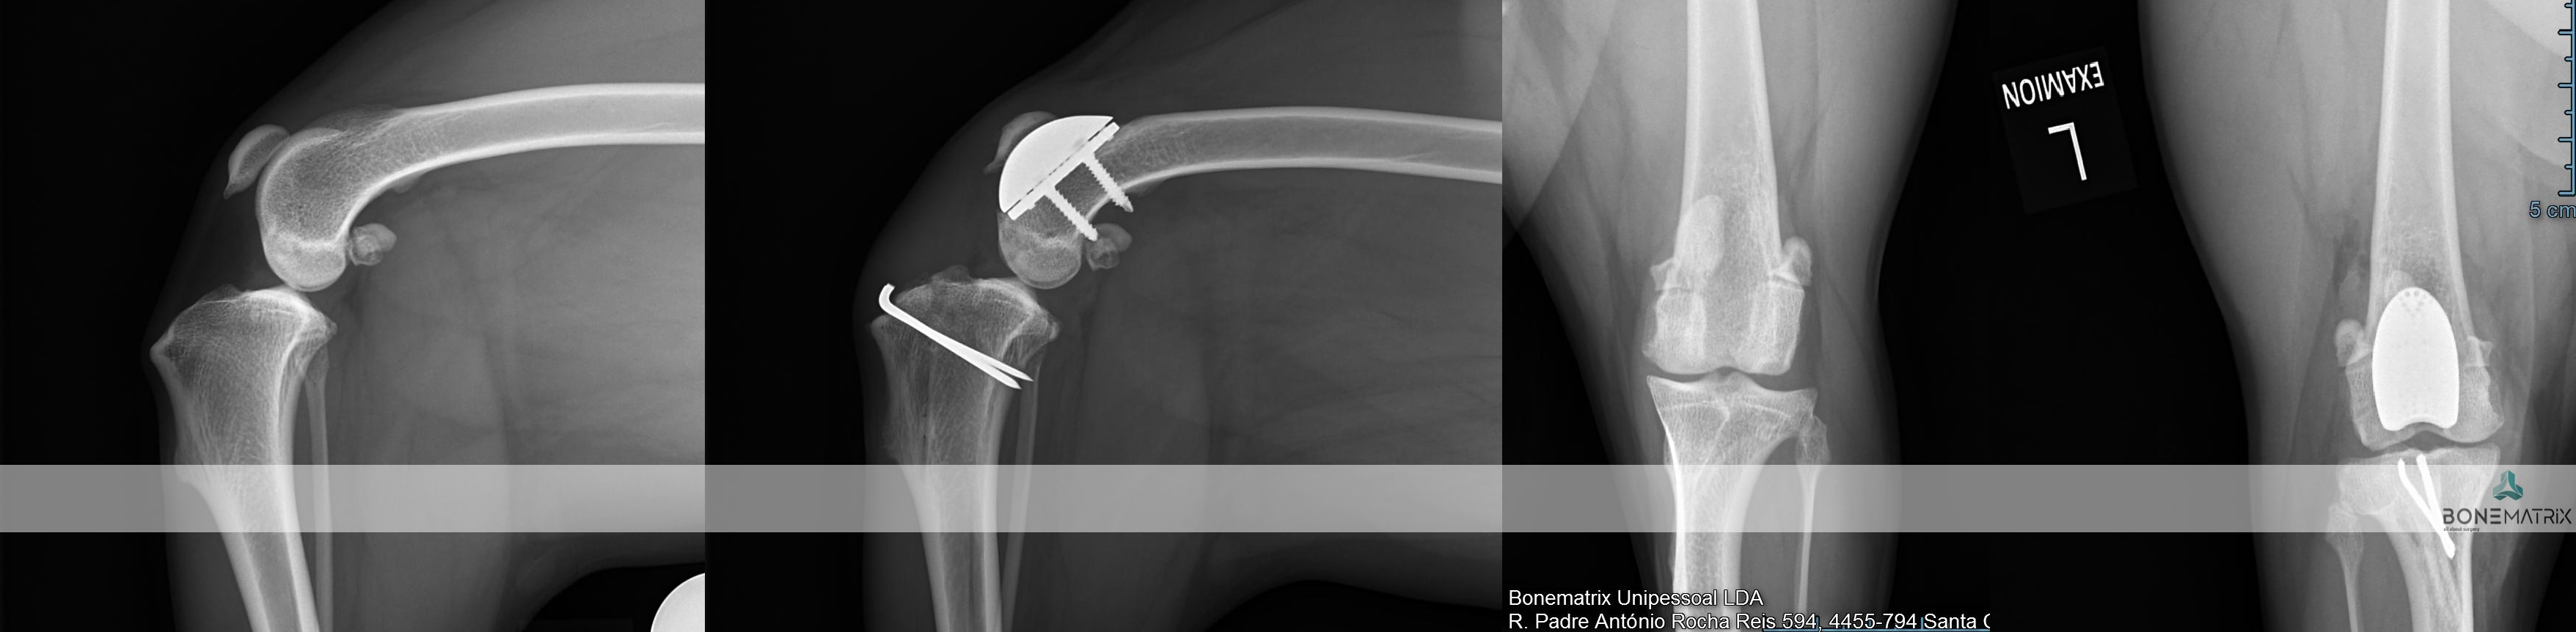

A Prótese Total de Anca (THR - total hip replacement) é um procedimento cirúrgico onde a articulação coxofemoral é completamente substituída por uma nova articulação protésica.

Em medicina humana, esta é a cirurgia de eleição utilizada como tratamento de quadros de osteoartrite severa, apresentando taxas de sucesso extremamente elevadas. Da mesma forma, esta é a solução mais avançada no paciente canino para o tratamento de osteoporose-artrite e displasia de anca, sendo a única capaz de restaurar uma função normal, com normal amplitude e ausência de dor.

Nem todos os pacientes são bons candidatos a THR pelo que os pacientes deverão começar por fazer uma consulta, com estudo radiográfico e avaliação da condição real de cada paciente em particular.

Os pacientes candidatos passam então a uma fase de estudo précirurgico, para que a cirurgia seja planeada com detalhe e se possam escolher a configuração e dimensão de implantes mais adequada.

A cirurgia consiste na eliminação das duas componentes articulares (cabeça femoral e acetábulo) com alterações patológicas e substituição por uma articulação protésica constituída também por duas peças que mimetizam a função da articulação anterior.

Qual a taxa de sucesso esperada?

Esta técnica de uma taxa de sucesso de 95%, sendo a taxa de complicações maiores cerca de 10%.

A restrição de exercício no pós operatório assim como a aplicação de uma boa técnica cirúrgica são fundamentais para o outcome cirúrgico.

DPO (double pelvic osteotomy) é um procedimento preventivo realizado em pacientes onde o despiste de displasia de anca prevê o desenvolvimento desta doença.

Inicialmente deve ser realizado um despiste de displasia de anca com recurso a um estudo radiográfico especifico para que o paciente seja avaliado e seja definido como um bom candidato à aplicação desta técnica.

O que é?

A DPO consiste na realização de dois cortes ao nível da pélvis que permitem a rotação do fragmento criado. Este fragmento inclui a porção articular da pélvis, na articulação coxofemoral (o acetábulo).

Ao rodar este fragmento conseguimos uma maior cobertura da cabeça femoral pelo acetábulo, impedindo o movimento de saída da cabeça femoral de dentro do acetábulo. Ao impedir este movimento (laxitude articular) impedimos o desenvolvimento de lesões de osteoartrite provocada por ele, e desta forma impedimos o desenvolvimento da doença de displasia de anca.

Após rotação do fragmento, este é estabilizado na posição pretendida com recurso a placas bloqueadas especializadas para a realização desta cirurgia, garantindo assim a cicatrização do osso no ângulo previamente definido.

Este procedimento pode ser realizado bilateralmente no mesmo momento cirúrgico.

Este procedimento deve ser realizado idealmente aos 5.5 meses daí aí importância dos despiste de displasia de anca serem realizados muito cedo na vida do animal.

Os pontos essenciais que definem um bom candidato são a idade do paciente, desenvolvimento mínimo de osteoartrite a nível articular e presença de um sinal de Ortolani positivo (teste realizado durante a consulta pré-despiste).

Após a realização desta cirurgia a claudicação irá resolver-se por norma em 3 meses após a cirurgia.

A taxa de sucesso de aplicação desta técnica é de cerca de 90% onde os paciente apresentam desde uma melhoria significativa até ao retorno à condição normal. Em alguns casos podem ser desenvolvidas alterações de osteoartrite ligeiras, mas por norma não são suficientes para provocar claudicação até que o paciente seja geriátrico.

Este procedimento preventivo é preferido a outras técnicas similares como a TPO por resultar num pós cirúrgico menos doloroso por comparação.